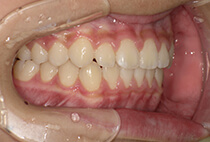

20代女性の患者さま。

八重歯の見た目が気になってご来院されましたが、実は顎の痛みや開口障害など、顎関節症の症状もありました。

そのため、かみ合わせと顎関節症の治療を同時に行ったにもかかわらず、2年間で治療が終了。

かみ合わせが整い咬筋の過緊張も改善しました。咬筋の肥大も治ってフェイスラインがすっきりしました。

最終的には美しい歯並びと、安定した痛みのないかみ合わせが実現しました。

しっかり前歯を下げるために、インプラントアンカーを使用してコントロールしました。

かみ合わせが整うと咬筋の過緊張が改善。

過緊張による筋肉肥大も改善しフェイスラインもすっきりしました。

治療前

治療後